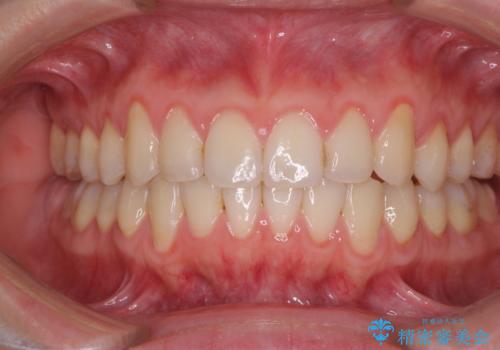

1日22時間の装着時間をしっかり守ってくださったので、予定していた1年よりも早く治療を終えることができました。

インビザライン矯正特有の奥歯がしっかりと咬合しない感覚も改善され、大変満足していただきました。